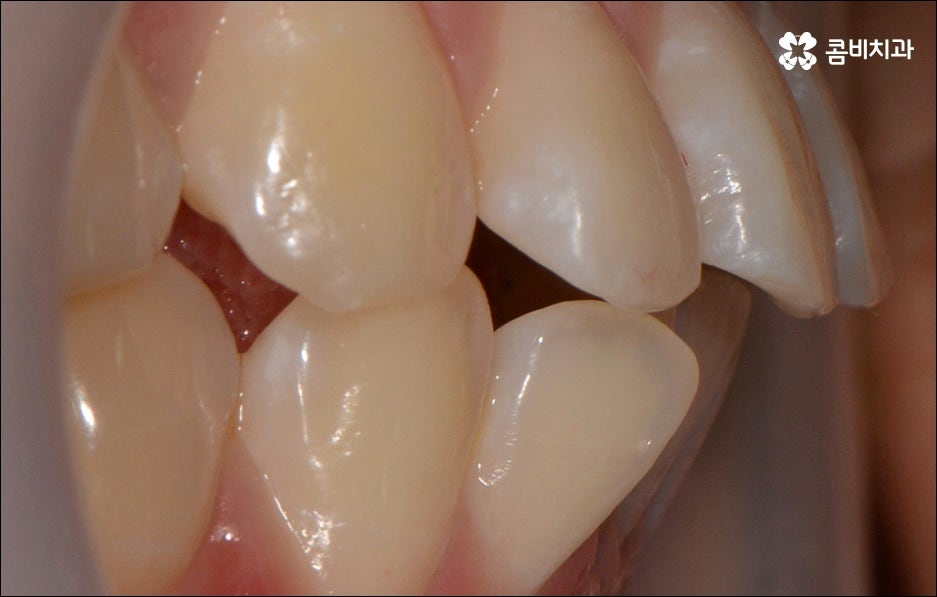

만약에 앞니 돌출 이 각도만의 문제라면 이를 교정하기 위한 치료는 좀 더 간단하게 끝날 수 있습니다. 말씀드렸던 것처럼 상황에 따라 보다 빠른 부분교정을 통해 앞니만 교정 치료를 진행할 수도 있을 거예요.

하지만 보통은 돌출된 앞니 뿐 만 아니라 골격적인 부분이 원인이 되는 경우가 많으며 이런 경우에는 상태에 맞게 전체적으로 교정을 진행하여야 교합이 올바르게 되고 입매가 전체적으로 균형감 있게 개선될 수 있어요. 이런 경우에 골격적인 원인을 무시한 채 무리하게 치아의 각도만 안쪽으로 넣으려고 하면 자칫 옥니가 될 수도 있기 때문에 이러한 부작용을 막기 위해서도 환자분들의 상황을 정확하게 검진하고 그에 맞는 교정 플랜을 세우는 것이 필요한 거예요. 물론 부정교합 정도가 심각하고 골격적인 원인이 이미 굳어진 경우와 같이 수술이 함께 필요한 케이스도 있을 수 있으나 교정 치료만으로도 튀어나온 앞니가 들어가면서 자연스럽고 부드러운 인상으로 바뀌는 경우도 많으니 먼저 검진과 상담부터 꼼꼼하게 진행해 보시길 권유드리고 있습니다. 특히 개개인의 치열, 교합, 잇몸 상태, 구강구조 등을 면밀하게 파악하고 그에 따른 정확한 치료 계획을 수립할 수 있는 경험 많은 의료진과 함께 하는 것이 중요할 수 있어요.